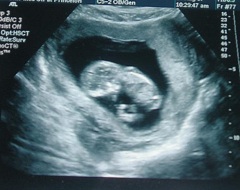

На УЗИ в 9 недель беременности можно заметить, что руки и ноги плода остаются непропорционально короткими, со сформированными уже пальчиками, на руках начинают закладываться ногти. Изменения затрагивают и лицо – глаза закрыты веками, широко расставлены, формируется ротовая щель. Ушные раковины на 9 неделе беременности уже хорошо различимы, но внутреннее ухо недоразвито, и плод еще не слышит.

Матка по УЗИ в 9 недель беременности размерами соответствует грейпфруту. Гормональная перестройка организма приводит к улучшению внешнего вида кожи – она становится более ровной и гладкой. Для благополучного течения беременности в крови увеличивается уровень женских половых гормонов и хорионического гонадотропина.